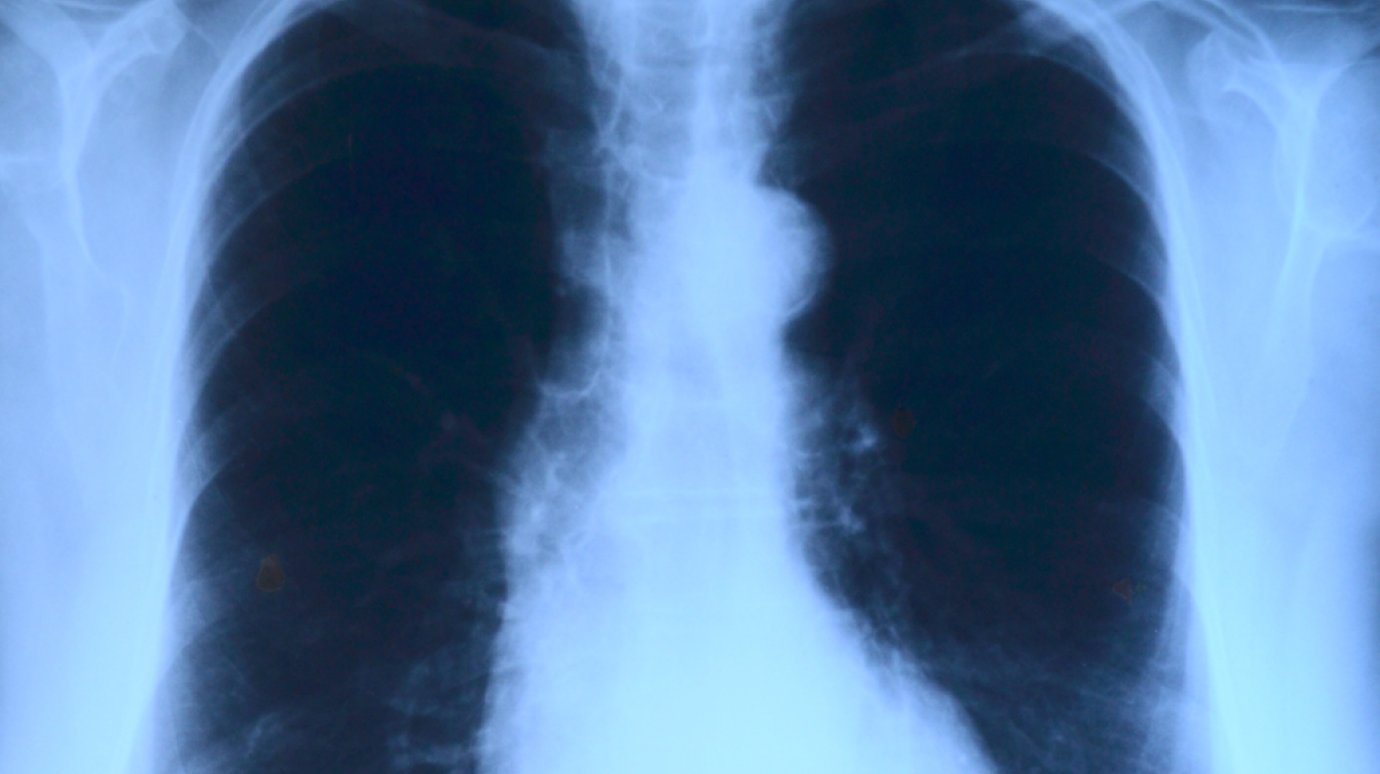

И нельзя не упомянуть открытие в 1895 году немецким физиком Вильгельмом Рентгеном X-лучей. Уже год спустя итальянцы Ботелли и Карбосса предложили использовать лучи Рентгена для диагностики туберкулеза легких и костей. По сей день усовершенствованная методика цифровой флюорографии является самым массовым способом диагностики туберкулеза у взрослых.

Имеются медицинские группы риска по туберкулезу. Это лица, которые состоят на учете с язвенной болезнью желудка и 12‑перстной кишки, бронхиальной астмой, пациенты с сахарным диабетом. Данной группе пациентов рекомендуется прохождение цифровой флюорографии раз в год. Флюорография выявляет малые формы туберкулеза, которые легче и быстрее поддаются лечению.

Основная профилактика для взрослых - это прежде всего флюорографическое обследование. Особенно нужно обратить на это внимание тем, кто не проходил флюорографию два года и более. Люди боятся облучения при прохождении обследования, но во всех медицинских организациях Пензенской области работают цифровые флюорографические аппараты. А взамен этого вы на весь год приобретаете спокойствие, что у вас нет туберкулеза, рака и других заболеваний легких.